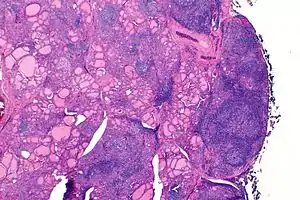

The thyroid of someone with Hashimoto's thyroiditis as seen with a microscope at low magnification

Marked lympocytic infiltration (purple areas) of the thyroid gland in a patient with chronic autoimmune thyroiditis

Gross pathology of a thyroid with autoimmune thyroiditis may show an symmetrically enlarged thyroid.[22] It is often paler in color, in comparison to normal thyroid tissue which is reddish-brown.[22] Microscopic examination will show infiltration of lymphocytes and plasma cells. The lymphocytes are predominately T-lymphocytes with a representation of both CD4 positive and CD8 positive cells.[22] The plasma cells are polyclonal, with present germinal centers resembling the structure of a lymph node.[22] Fibrous tissue may be found throughout the affected thyroid as well.[22] Generally, pathological findings of the thyroid are related to the amount of existing thyroid function - the more infiltration and fibrosis, the less likely a patient will have normal thyroid function.[22] In late stages of the disease, the thyroid may be atrophic.[12]

Histologically, the hypersensitivity is seen as diffuse parenchymal infiltration by lymphocytes, particularly plasma B-cells, which can often be seen as secondary lymphoid follicles (germinal centers, not to be confused with the normally present colloid-filled follicles that constitute the thyroid). Atrophy of the colloid bodies is lined by Hürthle cells, cells with intensely eosinophilic, granular cytoplasm, a metaplasia from the normal cuboidal cells that constitute the lining of the thyroid follicles. Severe thyroid atrophy presents often with denser fibrotic bands of collagen that remains within the confines of the thyroid capsule.[52]